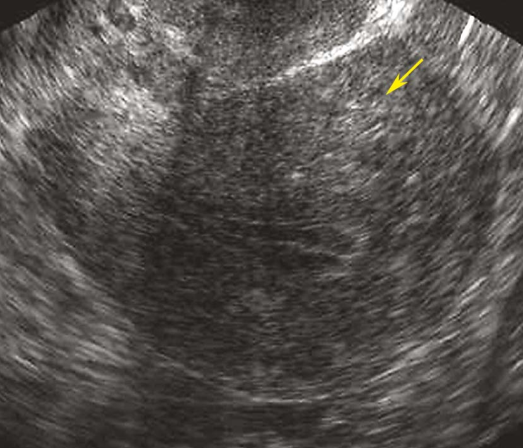

子宫腺肌病B型超声